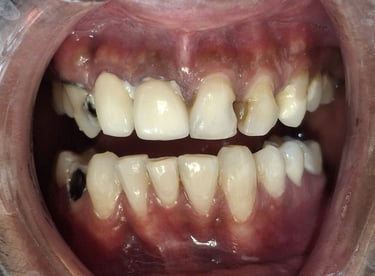

Before

After

All images shown here are real teeth cleaning cases treated at our clinic with patient consent.

Professional teeth cleaning helps remove plaque, tarter, and surface stains that regular at home brushing can not.

At Shree Dental Care, teeth cleaning is performed gently with focus on patient experience, comfort and long term oral health.